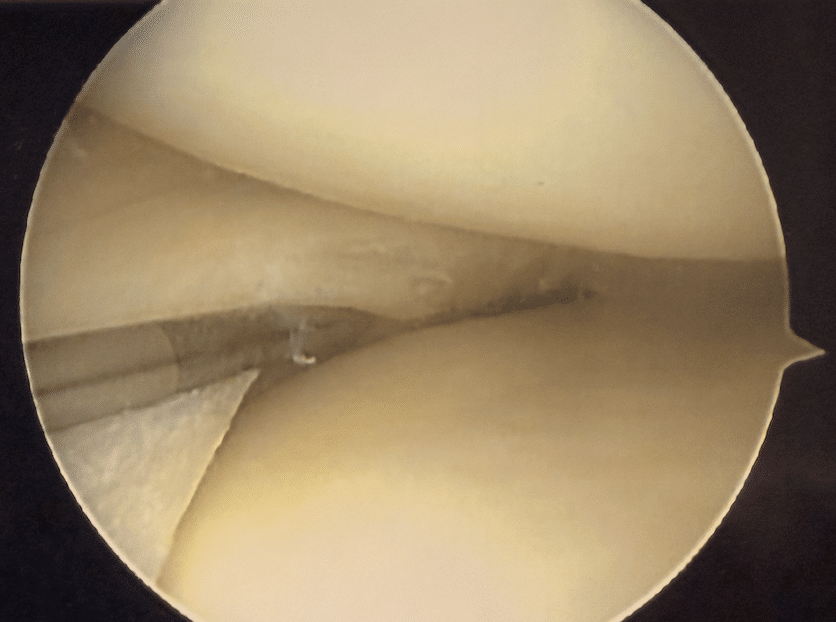

Nach einer ausführlichen klinischen Untersuchung und bildgebenden Diagnostik erfolgt die Arthroskopie in einem sterilen, minimalinvasiven Operationssetting. Mittels Millimeter kleine Hautschnitte wird ein Arthroskop, welches mit einer hochauflösenden Kamera ausgestattet ist, in das Gelenk eingeführt, um Strukturen wie Knorpel, Menisken, Bänder und Schleimhaut exakt darzustellen.

Über zusätzliche Arbeitskanäle können mikrochirurgische Instrumente eingebracht werden, um Knorpel- oder Meniskusläsionen, freie Gelenkkörper, entzündlich verändertes Gewebe oder Bandverletzungen direkt zu behandeln. Der unschätzbare Vorteil dabei ist, dass es zu keiner Verletzung des umgebenden Gewebes kommt, sodass schnelle Heilung und kaum Narbenbildung zu erwarten sind.